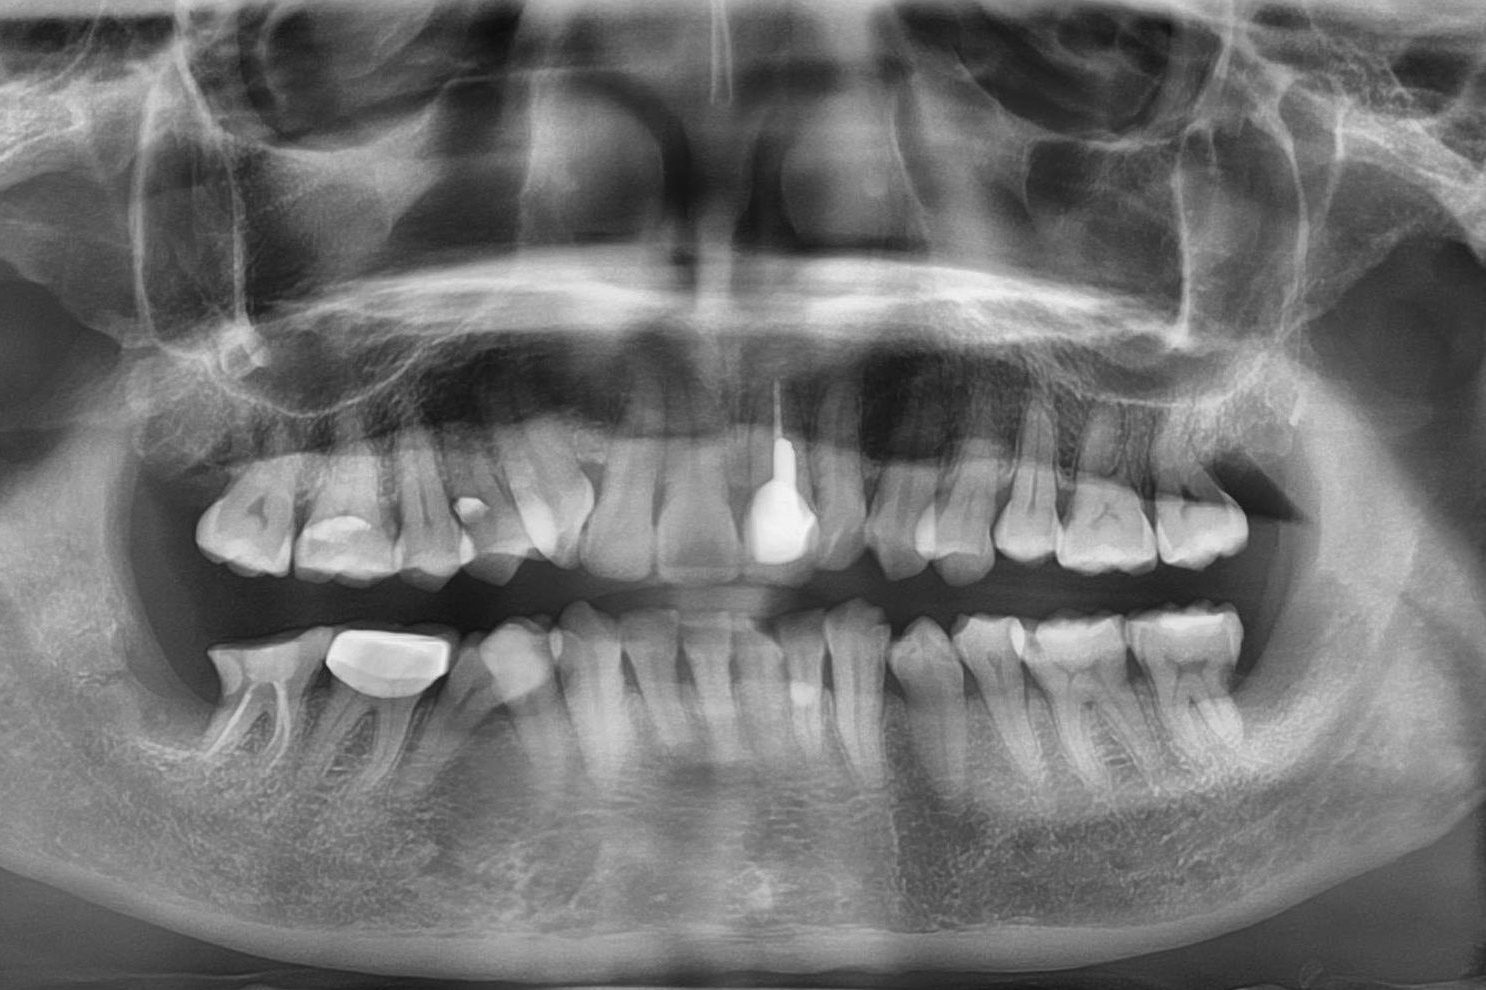

Chụp phim X-quang kỹ thuật số

Phân tích cấu trúc răng, tủy và xương quanh răng bằng công nghệ X-quang 3D, giúp đánh giá chính xác vùng tổn thương cần điều trị.